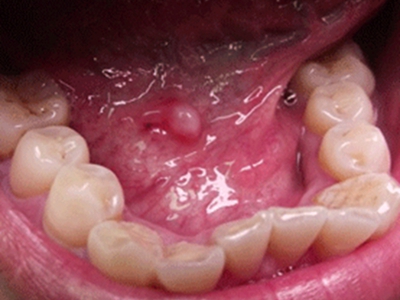

舌下腺囊肿舌头下面长了一个圆形肿块图

舌下腺囊肿位于舌底一侧,表现为圆形、光滑、柔软的肿块,直径约3cm大小,紧贴下牙,囊肿壁薄,呈浅紫蓝色,破裂并流出黏稠的液体。